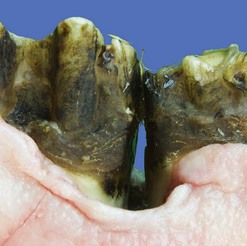

High levels of severe peripheral dental caries involving all classes of teeth (incisors, canines, and CT) have been found in groups of equids under certain management practices, such as feeding high concentrate, low roughage diets, where the reduced time spent masticating and decreased volume of buffering saliva may predispose to prolonged periods of low pH in the oral cavity and demineralization of calcified dental tissue. Peripheral caries is also concurrently found with other dental abnormalities, where restricted food and saliva movement may predispose to its development. Extensive generalized caries has also been recorded in horses fed diets with a low pH, where excessive acids were added to silage/haylage and also in diets consisting largely of simple carbohydrates, i.e., processed maize foodstuffs (Figs 10.37 & 10.38).

image

Fig. 10.37 Caudal maxillary cheek teeth from a horse with severe generalized peripheral caries and secondary fractures and periodontal disease associated with feeding an almost total processed maize diet.